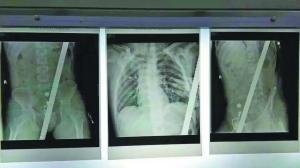

医生检查发现,钢筋从裆部插入,穿过腹部、胸部,又从左边肩胛骨穿出。由于体外钢筋过长,崔先生无法进行CT机拍片诊断伤情,医护人员只得请来消防员剪断钢筋,以便手术治疗。

崔先生的主刀医生,该院创伤外科副主任梁旭光表示,崔先生被送进医院时神志清醒,检查结果显示钢筋未刺破重要脏器,随后为其紧急进行剖腹手术。“钢筋是螺旋纹状的,有1.8厘米粗。”梁旭光说,多名专家会诊后确定了手术方案。手术中,医生先剖开病人腹部,找到钢筋穿过的位置,再由各个科室分工,四名医生护住病人主要脏器,再由另一名医生慢慢抽出钢筋。经过一个多小时的努力,终于将没入体内长约70厘米的钢筋取出。